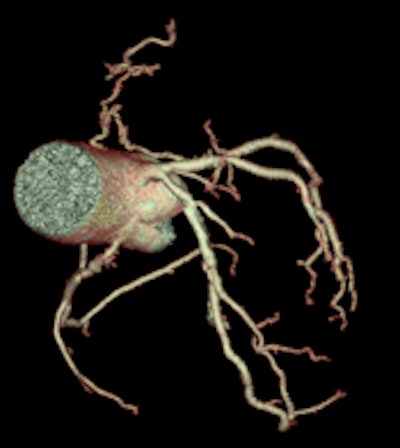

High-definition cardiac CT image obtained on GE Healthcare's Discovery CT750 HD shows bronchial vessels. (Provided by GE)

With its latest technology on display here in Vienna, GE Healthcare aims to tackle some of the specific challenges faced in conducting CT examinations on cardiac patients, including coronary motion, high heart rates, plaque composition, and accurate perfusion. Its Discovery CT750 HD Freedom Edition offers capabilities that could "change the rules" of cardiac CT. Based on the FREEdom (Fast Registered Energies and ECG) technologies, the system is designed to offer major innovations, including intelligent motion correction, improvements in calcium visualization, plaque material composition assessment, and more accurate perfusion calculations.